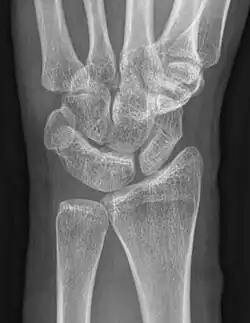

Karpale Koalition

Eine karpale Koalition ist eine feste Verbindung zwischen Handwurzelknochen, die normalerweise über ein Gelenk in Kontakt stehen. Dabei kann diese Verbindung knöchern (Synostose), knorpelig (Synchondrose) oder bindegewebig (Syndesmose) ausgebildet sein. Als Ursache wird von einer mangelhaften Differenzierung der Handwurzelknochen zwischen der 4. und 8. Embryonalwoche ausgegangen[1].

Wenn eine karpale Koalition isoliert auftritt, was der häufigere Fall ist, sind in der Regel zwei Knochen der gleichen Handwurzelreihe betroffen, beim Auftreten im Rahmen von Syndromen oder anderen globaleren Störungen treten auch Verbindungen von mehreren Knochen beider Reihen auf[1][5]. Die bei Weitem am häufigsten verschmolzenen Knochen der Handwurzel sind Os lunatum und Os triquetrum gefolgt vom Os hamatum mit dem Os capitatum[1].